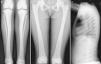

Varón de 10 años, natural de Marruecos, remitido para estudio por discapacidad intelectual. Su hermana mayor también presentaba una discapacidad intelectual de etiología no filiada. Exploración física sin hallazgos, entre los antecedentes personales destaca la existencia de fracturas de repetición. En las pruebas complementarias se objetiva acidosis metabólica (pH 7,196, presión parcial de dióxido de carbono [pCO2]) 42,1mm de mercurio [mmHg], potasio 4 milimoles/litro [mmol/l], gradiente transtubular de potasio 8,47, bicarbonato [HCO3] 15,7 mmol/l, exceso de bases [EB] –11,8 mmol/l) con anión gap plasmático: +10,5 y anión gap urinario 103. Ante la sospecha del origen renal de la misma, se procedió a realizar una prueba de alcalinización de la orina con bicarbonato y acetazolamida, obteniendo en sangre un pH 7,29, pCO2 31,4mmHg y en orina pH 7,87, bicarbonaturia 92 miliequivalentes/l, osmolalidad urinaria 982 miliosmoles/kg y pCO2 de 60,7mmHg, con lo que se obtiene un delta de pCO2 de 29,3mmHg, que podría corresponder con un defecto de acidificación distal. No se valoró la posible afectación en la reabsorción tubular proximal de bicarbonato. La serie ósea (fig. 1) mostraba hallazgos compatibles con osteopetrosis. Dado los antecedentes familiares, se solicita el estudio analítico y radiológico a su hermana (fig. 2) con resultados similares. Ante la sospecha de osteopetrosis asociada a acidosis tubular y la relación de esta con la presencia de calcificaciones intracraneales1,2, se realiza tomografía axial computarizada cerebral con hallazgos compatibles en ambos hermanos (fig. 3). Finalmente se confirma el diagnóstico mediante secuenciación del gen CA2, donde se encuentra la mutación patógenica3 c.232+1G>A en homocigosis en ambos hermanos. No presentaban la sordera que frecuentemente asocia esta entidad1. En la actualidad, se encuentran en tratamiento con bicarbonato asociado a citrato potásico para corregir la acidosis.

Serie ósea: deformidad de huesos largos, esclerosis cortical y reducción de la cavidad medular (a, b). Ensanchamiento de las metáfisis y diáfisis femorales con morfología en «maza» o de «Erlenmeyer flask» (b). Cuerpos vertebrales con esclerosis de la placas terminales e hiperlucidez central o signo de la vértebra «sándwich» (c).